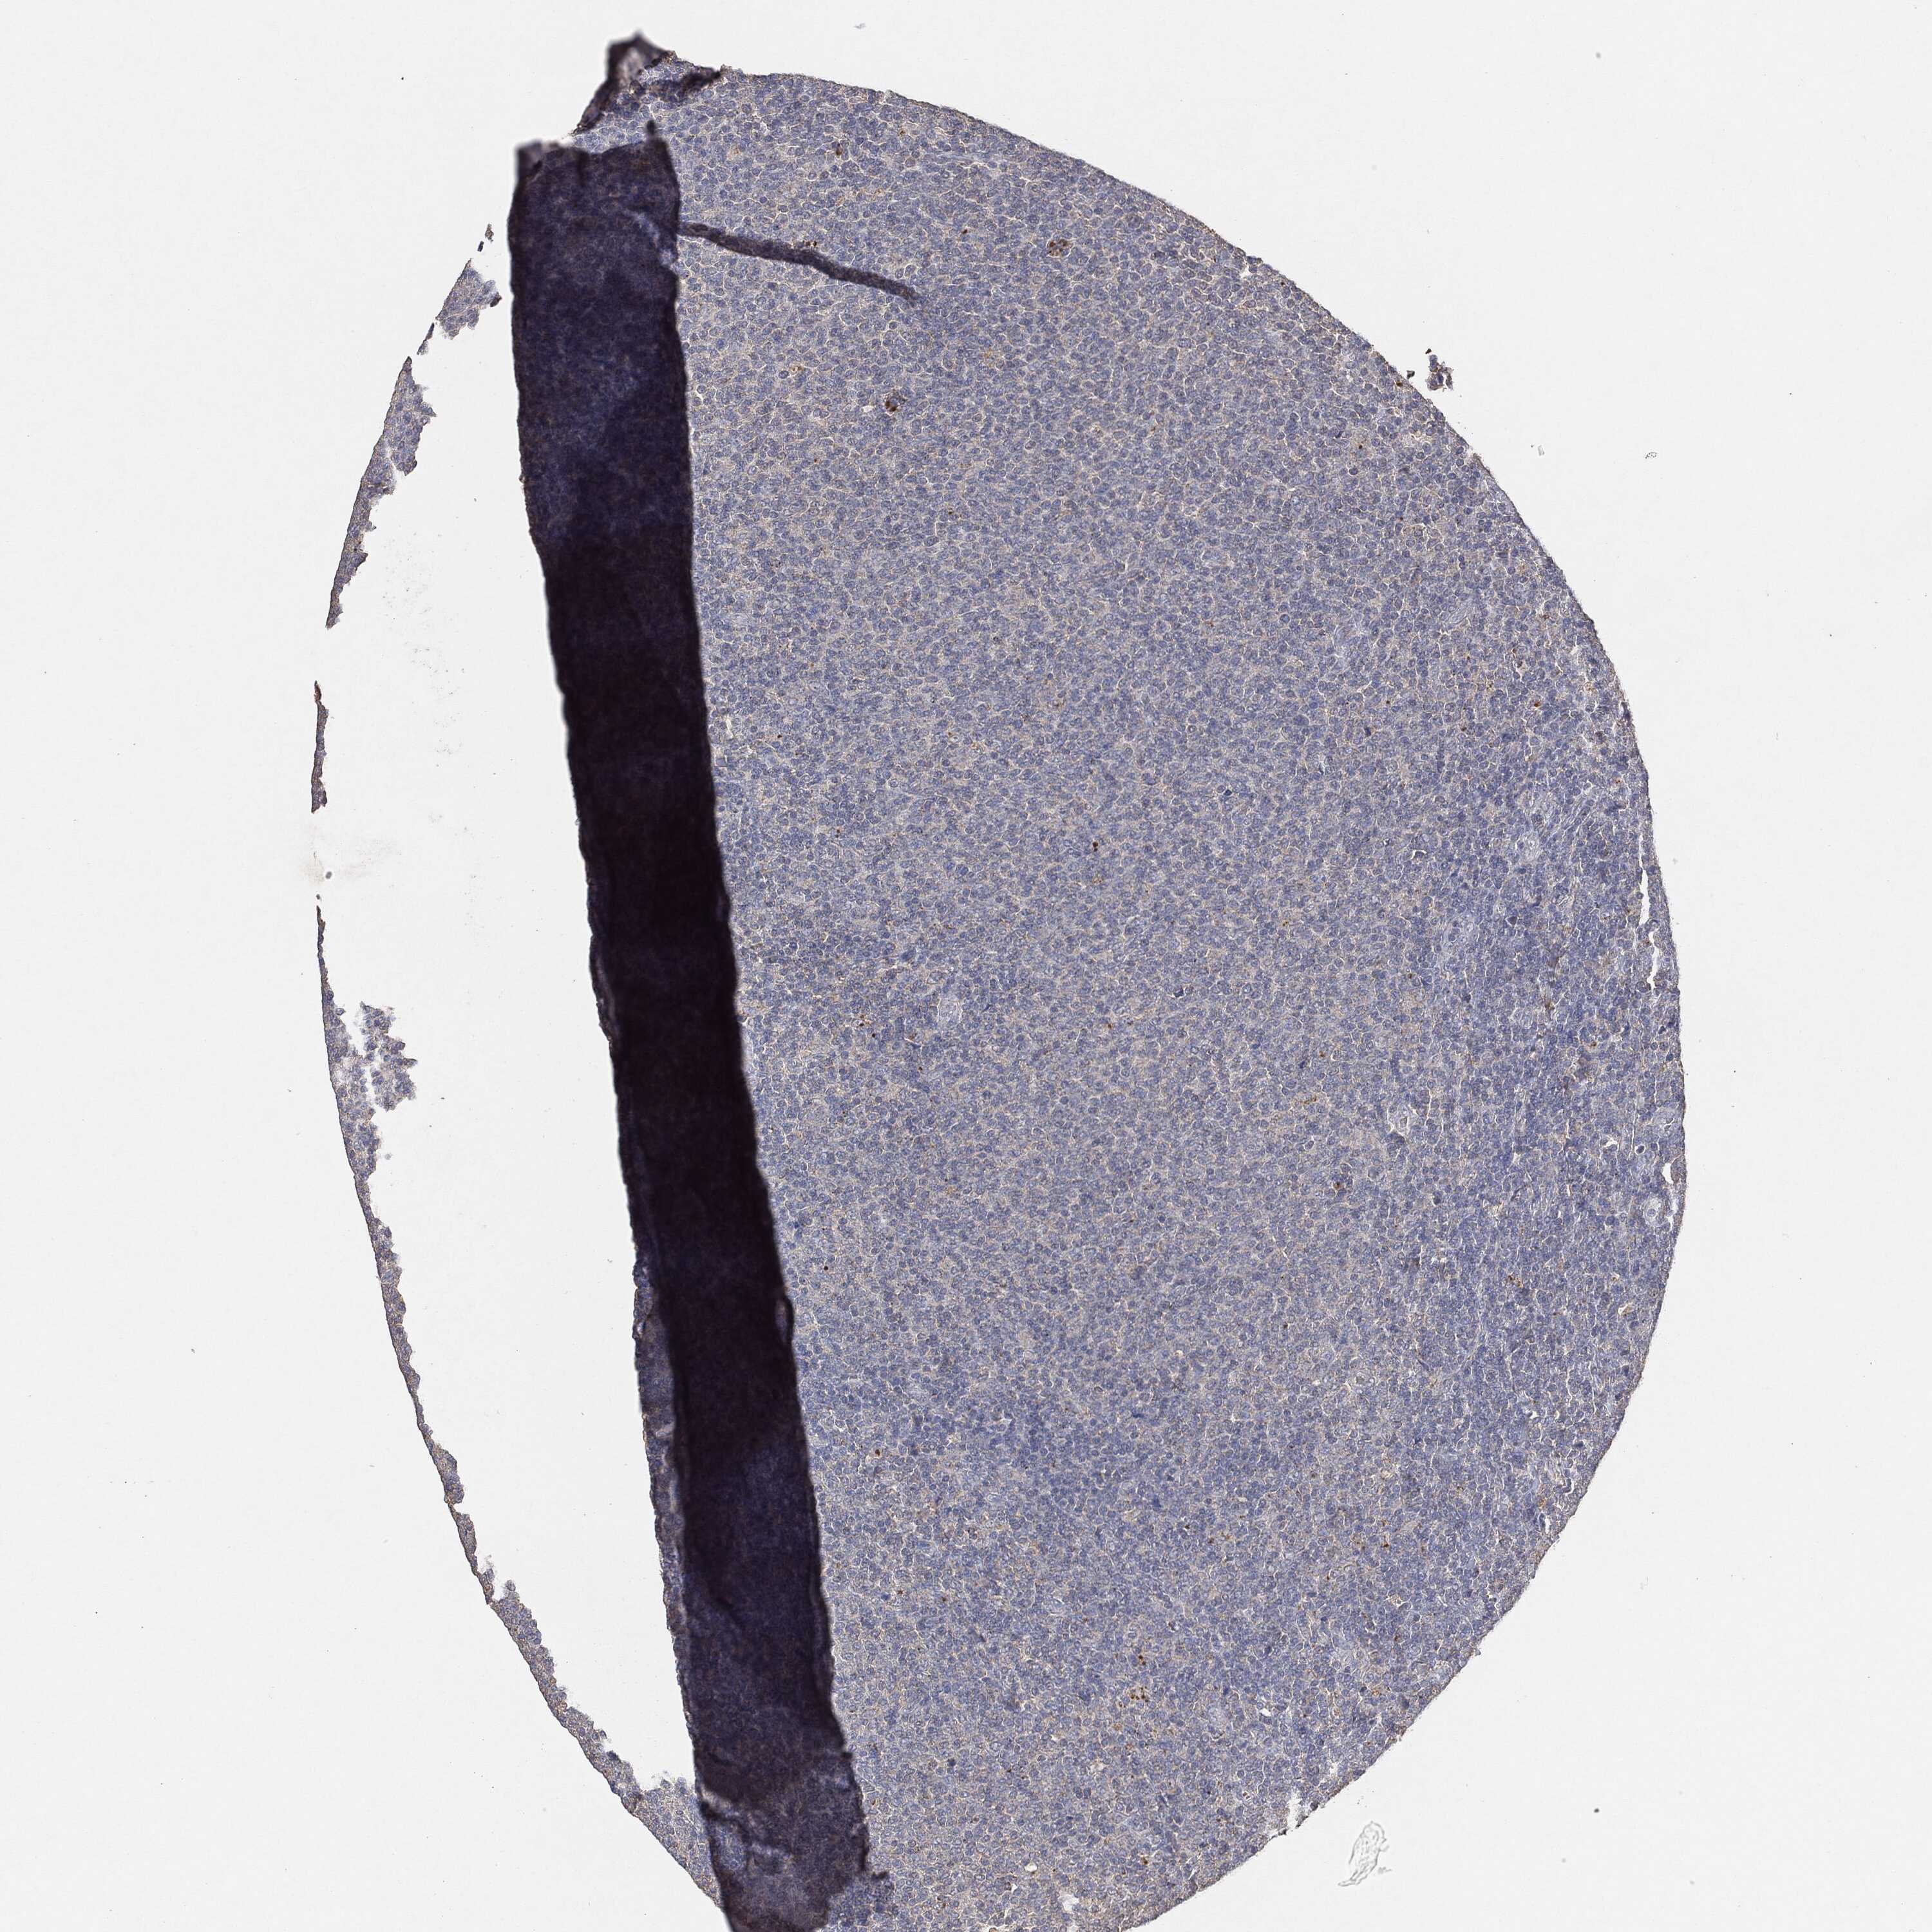

LYMPHOMA - Protein expressioni

A mouse-over function shows sample information and annotation data. Click on an image to view it in a full screen mode. Samples can be filtered based on level of antibody staining by selecting one or several of the following categories: high, medium, low and not detected. The assay and annotation is described here.

Note that samples used for immunohistochemistry by the Human Protein Atlas do not correspond to samples in the TCGA dataset.

Antibody stainingi

Antibody staining in the annotated cell types in the current human tissue is reported as not detected, low, medium, or high, based on conventional immunohistochemistry profiling in selected tissues. This score is based on the combination of the staining intensity and fraction of stained cells.

Each image is clickable and will lead to virtual microscopy that enables deeper exploration of all samples and also displays staining intensity scores, fraction scores and subcellular localization as well as patient and tissue information for each sample.

Malignant lymphoma, non-Hodgkin's type, High grade

Hodgkin's disease, NOS

Malignant lymphoma, non-Hodgkin's type, Low grade